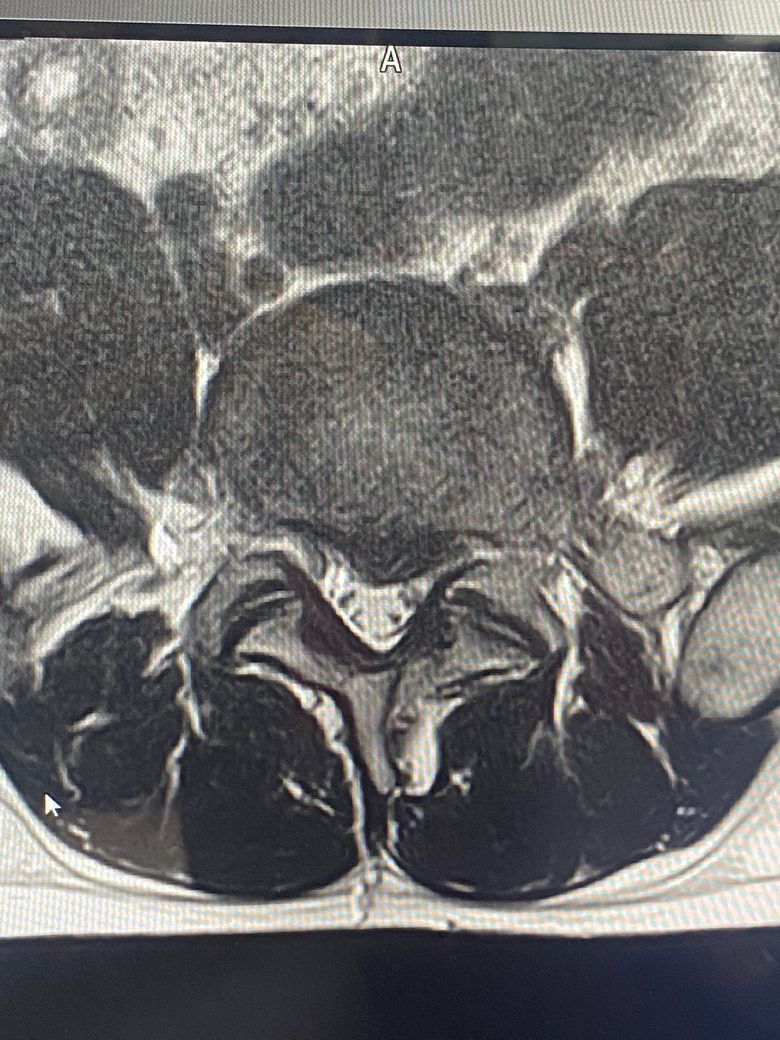

• 1번 째 사진

MRI는 3컷만으로 평가할수 없지만 현 상태상 허리 디스크 탈출증이 의심됩니다.

• MRI 단면 몇 장으로 정확하게 상태를 평가하기는 어렵지만 요추 4번의 디스크 돌출 및 그로 인한 척수의 눌림이 발생한 것으로 사료됩니다. 방사통이 있는 상태에서는 심한 운동을 할 때에 디스크 증상을 오히려 악화시킬 수 있기 때문에 현재 상태에서 바로 헬스를 하시기 보다는 식이요법과 걷거나 가볍게 뛰는 정도의 운동을 통해서 체중 감량을 하시고 통증에서 자유로워 지면 그 때에 피트니스나 필라테스 등을 통해서 직립근 등 코어 근육을 강화해주시는 것을 추천드립니다.